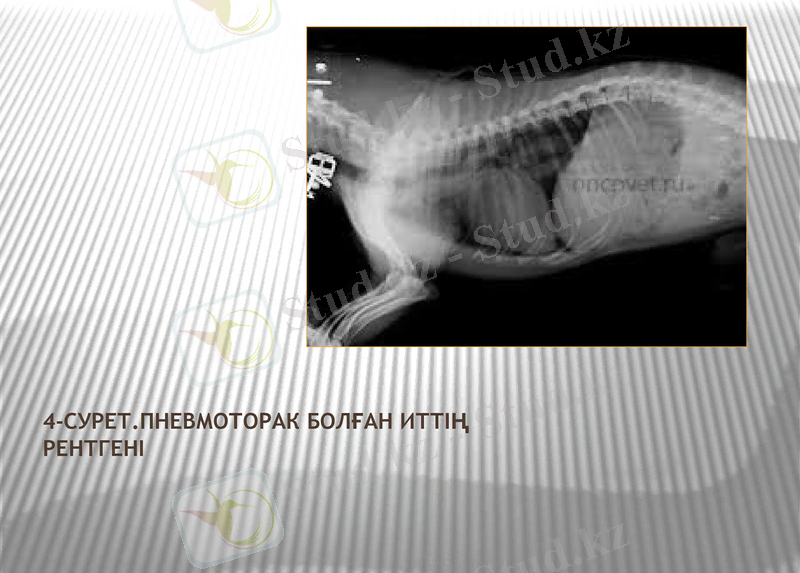

Анамнез және клиникалық белгілердің негізінде қойылады. Рентгендік тексеру арқылы плевральды қуыста ауа жиналған жерлерде, ал өкпенің түсу орындарында - көлеңкеленген учаскелер анықталады. Дифференциалды диагнозда плеврит, гемоторакс, гидроторакс болмайды. Диагнозды анықтау және плевроцентездің ішіндегісінің сипатын анықтау үшін жүргізіледі.

4-сурет. Пневмоторак болған иттің Рентгені